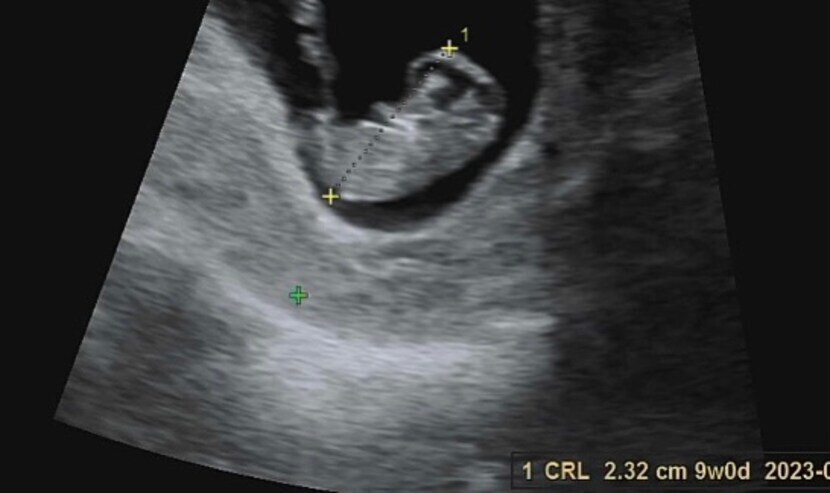

κΈ°λ€λ¦¬κ³ κΈ°λ€λ¦¬λ λ³μκ°λλ β€

λλ μκ³ μμ€νβ€

μ¬μ₯λ κ½λ±κ½λ±

λ μ¬κΈ° μμ΄μ~